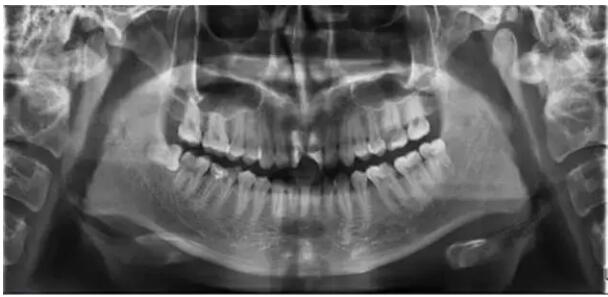

通過(guò)全面詢(xún)問(wèn)病史,臨床檢查和拍攝X光片,結(jié)合患者的主觀癥狀、身心狀態(tài),擬定治療方案,充分進(jìn)行醫(yī)患交流并詳細(xì)記錄。